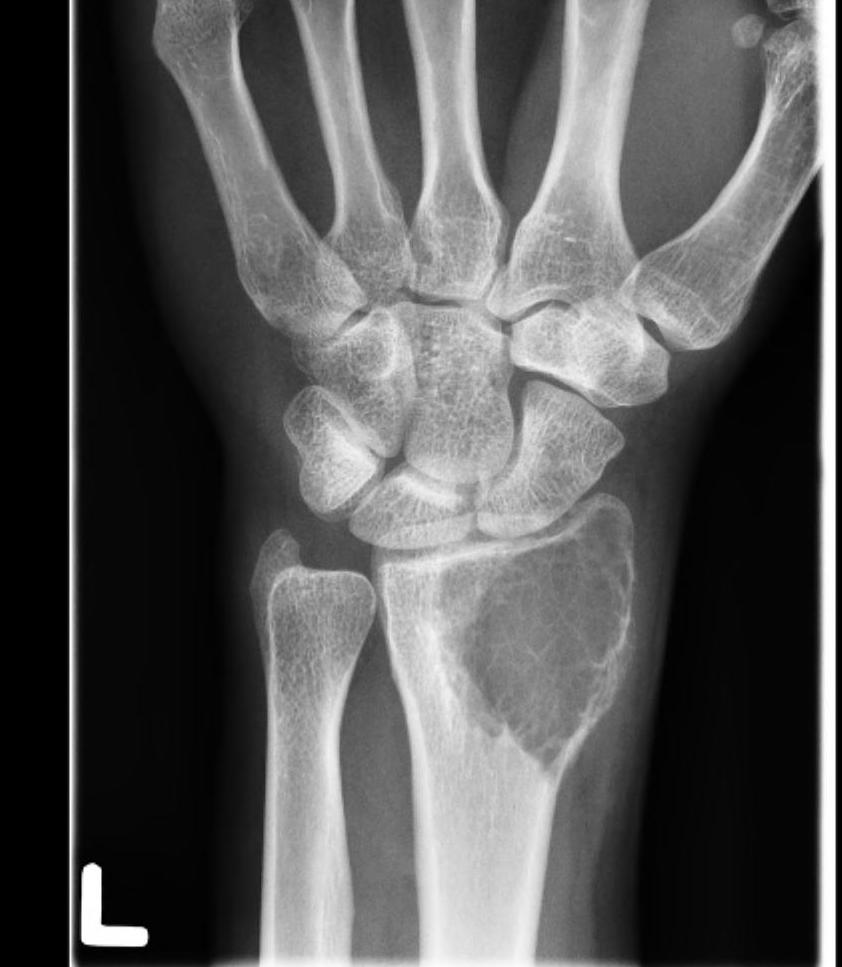

Wrist / Hand

Carpus / metacarpal / phalanges - dorsal approach